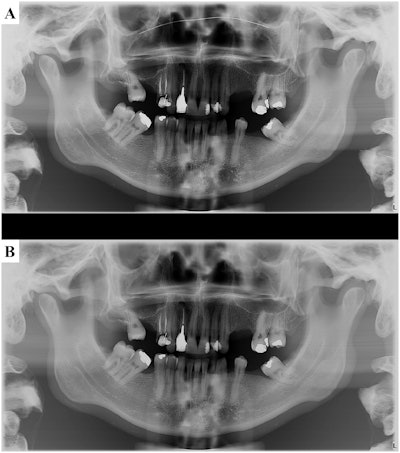

To that end, one factor to note is that most face masks include a nose wire. This can lead to the generation of metal artifacts that decrease image quality during conebeam CT. Simply remove the wire from the mask before image acquisition to avoid the superposition of its image on the nasal cavity and maxilla, the team suggested.

"After positioning the patient's chin on the chin rest, the professional should instruct the patient to bite a disposable item such as a wood stick to promote disocclusion and avoid the overlap of the crowns of the upper and lower teeth," the team wrote.

Then, the midsagittal plane and the patient's canine prominence, which can be palpated without the need to remove the mask, must be aligned with the laser lights of the x-ray device, they instructed.